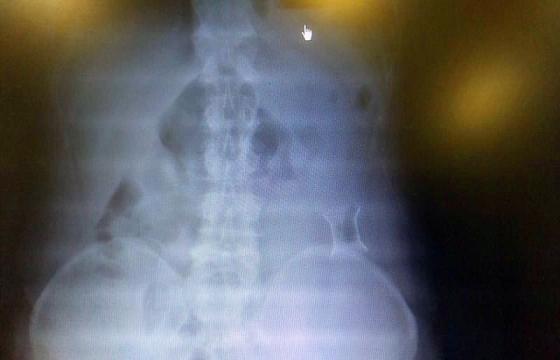

受試患者在結(jié)腸端端吻合術(shù)中,使用我司新研制產(chǎn)品達到了理想的預期效果。患者術(shù)后7天、14天X光片顯影,可降解腸道支架均能按研制設(shè)計的預期時間節(jié)點保持應(yīng)有強度,術(shù)后21天X光片顯示可降解腸道支架已完全破碎,并排出體外。在整個試驗過程中,病患無任何不良反映,耐受良好。